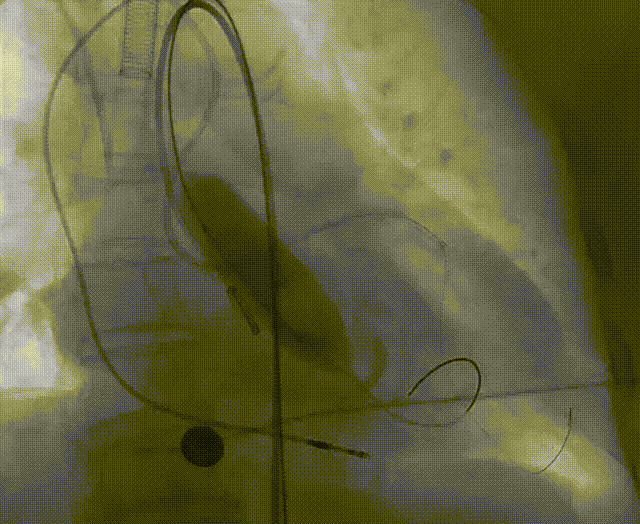

左冠脉提前植入延长导管,预埋冠脉导丝。

20mm球囊预扩张,无腰征,无造影剂泄露。

vitaflow tav24瓣膜轻松过弓初始定位瓣环0位开始释放,班第一次释放瓣膜在转移到瓣上,综合决定回收采取第二次瓣膜释放。

第二次精准零位释放,决定完全释放。

释放后多体位观察造影,瓣膜位置良好,展开良好,轻微瓣周漏。